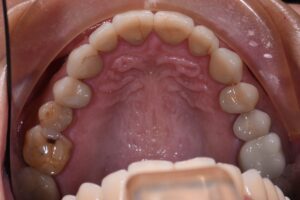

December 20, 2021 A little Christmas occlusal rejuvenation maintaining the current MI. #TheShinEffect #IPSemaxMT #emaxCeram #BiteLabMixingDeck Previous Post Next Post